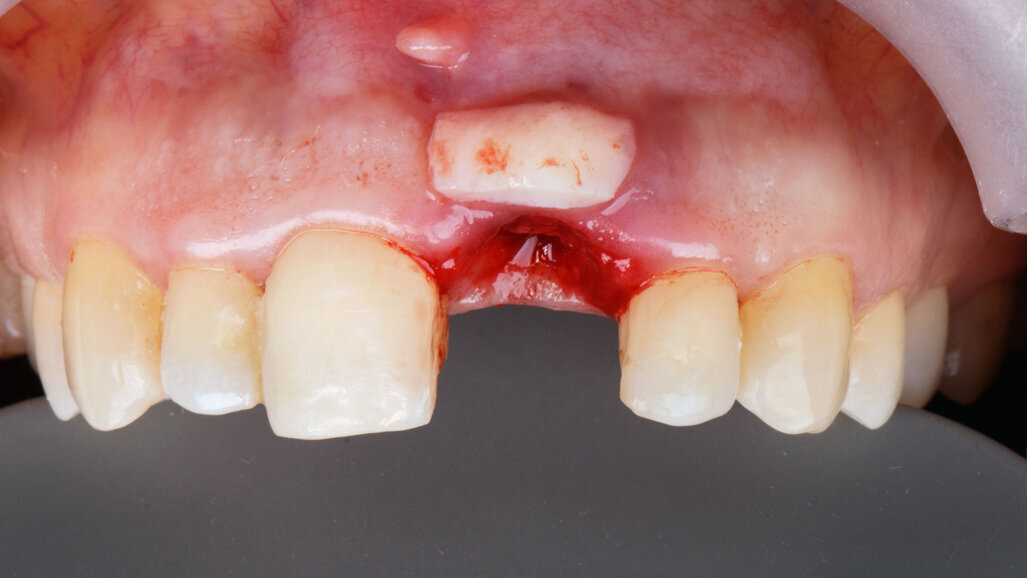

Može li augmentacija mekog tkiva oko implantata utjecati na uspjeh implantoprotetske terapije u smislu očuvanja kosti i estetike?

Odgovor na ovo pitanje ...